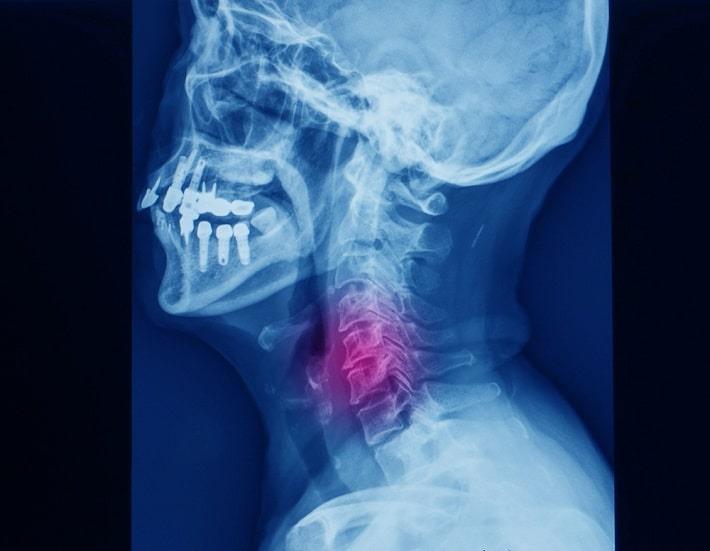

צילום: Yok_onepiece | shutterstock

צילום רנטגן - צילומי רנטגן של עמוד השדרה הצווארי הם בדיקות ההדמיה הנפוצות ביותר להערכת כאבי צוואר וגפיים עליונות.